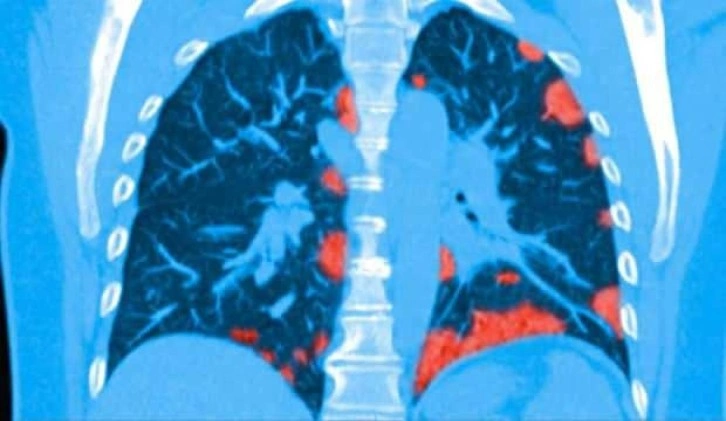

National Geographic’in yayınladığı fotoğrafta Kovid-19’u ağır geçiren hastanın akciğerlerindeki damarların ciddi bir şekilde hasar gördüğü görülürken, birçok damarın ise tıkandığı açıkça gözler önüne seriliyor.

Yayımlanan fotoğrafta açık renkli damarların hava aralığı olduğu belirtilirken, kırmızı damarlar ise açık kan damarları olarak görülüyor. Taramada sarı renkte gösterilen damarlar ise Kovid-19 sebebiyle tıkanmış damarları açıkça gösteriyor.

HiP-CT tarama yönteminde 54 yaşında Kovid-19’dan yaşamını yitiren bir adamın akciğerlerinde hasar bilim insanlarını şaşkına çevirdi.